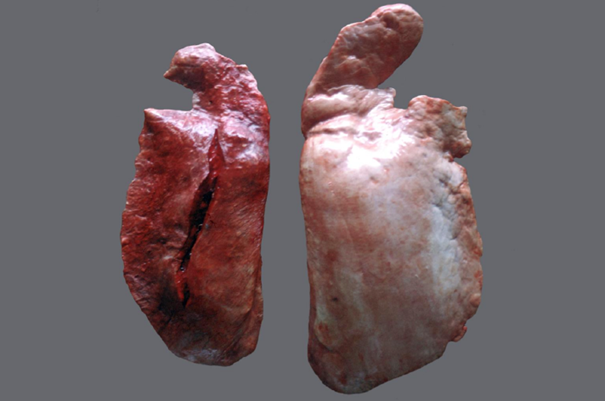

Rind, Lunge: hochgradige, akute bis subakute, multifokale, fibrinöse Pleuropneumonie

Beschreibung:

- Inset: kranioventral finden sich Parenchymund Pleuraveränderungen

- multifokale, gelblichrötliche Matten auf der Pleura (= Fibrin)

- Schnittfläche des Parenchyms: Läppchenbezogene Muster mit bunter Marmorierung

- die betroffenen Läppchen sind verfestigt

- einige Läppchen wirken trocken, andere Läppchen geben auf Druck dunkelrot- gräuliche Flüssigkeit frei

- Interstitien teilw. verbreitert und sulzig

Links (nur eine Hälfte) = A

Rechts (beide Hälften) = B